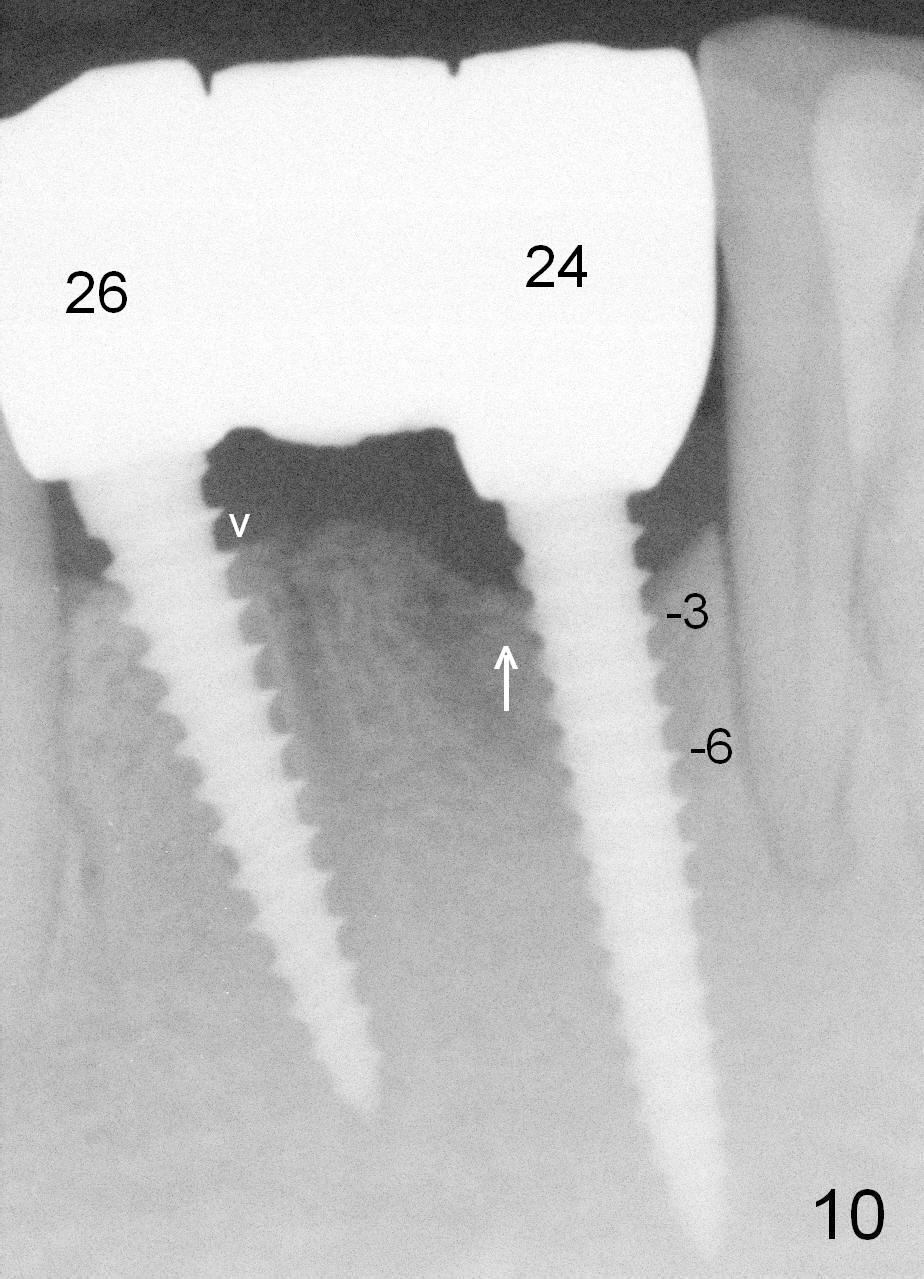

Fig.7 shows these two one piece implants immediately prior to cementation of the FPD (Fig.8). They are much more parallel to each other after prep, as compared to Fig.6. Fig.9 shows apparent bone growth around #24 implant (at the crest) 6,9 months post cementation and surgery, respectively. Orthodontic treatment will incorporate the fixed partial denture. Fig.10 shows that bone grows coronally (arrow) to cover 3 threads (from #6 thread to #3) at the site of #24 one year after functioning. There is mild buccal gingival infection involving #26 retainer. Preop CBCT is reviewed to determine whether it is related to potential thread exposure. It appears that at the sites of #24 (Fig.13,14) and 26 (Fig.11,12), 2.5 mm implant is more appropriate for the narrow ridge than 3.0 mm one. In fact, periimplantitis develops at #26 two years of absence of perio maintenance (because of atrial fibrillation with blood thinner; Fig.15, 3 years 7 months post cementation). Periimplantitis persists 4.5 months later. Although water pik is purchased, it is not used often because of low blowing force. If needed, remove the FPD atraumatically. Unwind the implant, clean the coronal threads with Titanium brush or remove the exposed threads and replant the implant with bone graft.